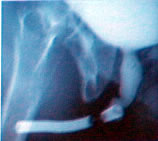

После простатэктомии

по поводу ДГПЖ |